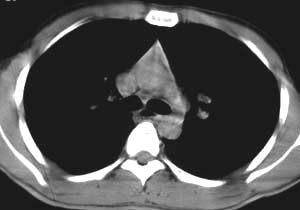

标题: CT5150:左上肺空洞病变,肺撕裂伤? [打印本页]

标题: CT5150:左上肺空洞病变,肺撕裂伤?

左侧锁骨骨折,患者主诉未伤及胸部,无其他病史。

该病灶在纵隔窗没有显示,说明是渗出性病变,而且肺窗看起来也显得它非常淡薄。能造成锁骨骨折,说明受伤时所受冲击力不小。在大冲击力的情况下,胸部发生碰撞的机会非常大,很多患者在受伤后都说不清自己究竟是怎么着地以及究竟是何种姿势受伤。

从病灶特点分析应该是渗出性病灶,但有一点不好解释.病灶中心有空洞,而且不规则,空洞边缘似见硬化或钙化.因此考虑:肺挫伤同时不除外特殊感染性病灶.